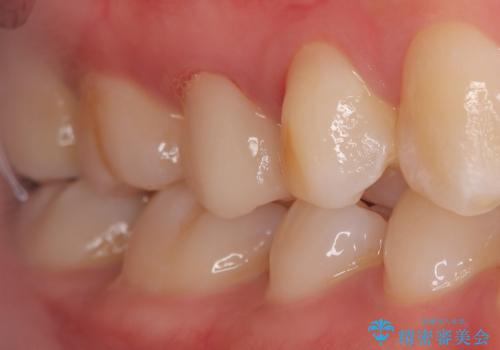

- 主訴:他院で根っこの治療を行っていたところ、根が細く治療が難しいと言われてしまった

右上5番目の歯が根管治療途中となっており、前医院にて根管が狭く治療が難しいと言われてしまいセカンドオピニオンで当院にいらっしゃいました。

右上5番レントゲン写真上では根管が確認しずらく、根管の狭窄が予想されました。マイクロスコープを使用し、根尖部まで器具を到達させ十分根管洗浄を行うことができました。